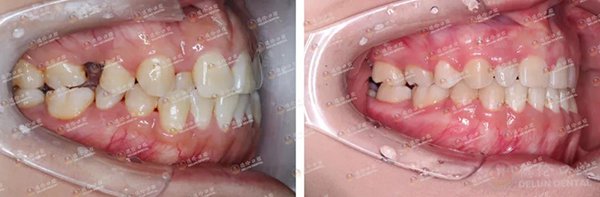

朱女士矫正前(左)与矫正中(右)对比图。朱女士希望通过矫牙将牙齿排列整齐、改善面型,并关掉明显的牙缝

庄女士矫正前(左)与矫正中(右)对比图。庄女士拔除了一颗严重蛀掉无保留价值的残根后开启矫牙之旅。李医生将庄女士的阻生智齿扶正前移,代替那颗被拔掉的残根